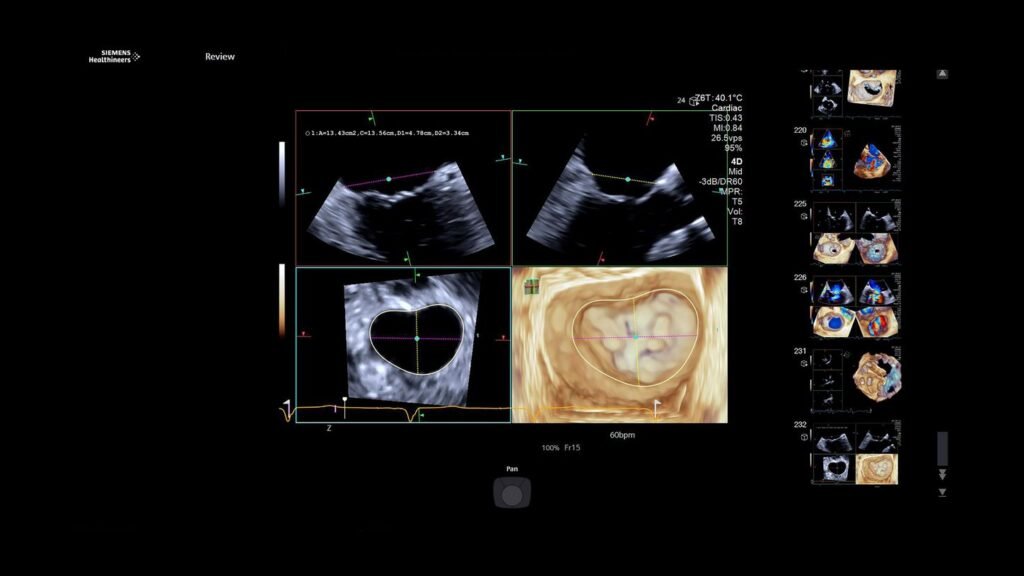

Škola ehokardiografije Dom zdravlja Grude

November 30, 2025

U organizaciji domova zdravlja i kantonalnih udruženja ljekara Hercegovačko-neretvanskog i Zapadnohercegovačkog kantona, 8. novembra 2025. godine u Domu zdravlja Grude održana je cjelodnevna Škola elektrokardiografije namijenjena…